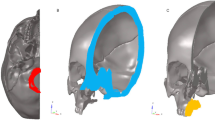

Three-dimensional finite element analysis (FEA) was used to examine deformation and stress-strain response of the anatomical model of the skull under the applied osteotomies and the distractor load before the surgery. The skull was segmented with MIS software (Mimics Innovation suite V20.0, Materialise NV, Leuven, Belgium) which allows analysis of individual differences of bone thickness (Fig. 1).

A partially or complete opening of the lateral sinus wall and disconnection of the midpalatal suture, as advised by Lines, could be performed individually in the software environment (Fig. 2). Mesh refinement and mesh smoothing were generated to ensure a high finite element quality. An input file with the FE mesh was exported for the solver. The tetrahedral mesh file was imported into the ANSYS Mechanical APDL software application. With the programming language APDL (ANSYS Parametric Design Language), the definition of material properties and boundary conditions was performed. For the bone material, Poison’s ratio of 0.3 and a modulus of elasticity of 15000MPa are defined. The transversal distraction of both palatal halves was simulated by applying a force of 150N at the endpoints of the distractor which were individually adjusted.

The whole workflow with the meshing of bone geometry, the finite element model generation, and the simulation was performed automatically (Fig. 3).

The simulation results were then used to create an individual surgical guide (ANSYS SpaceClaim software ANSYS Inc., Canonsburg, USA) for the left and right sides via CAD/CAM technique and subsequently milled (Hermle C30U, Maschinenfabrik Berthold Hermle AG, Gosheim, Germany) from PEEK (polyetheretherketone) [28, 29] (Fig. 4).